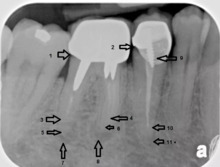

An X-ray explanation of bad root canal therapy

X-ray explanation of bad root canal therapy

Another common complication of root canal therapy is when the entire length of the root canal is not completely cleaned out and filled (obturated) with root canal filling material (usually gutta percha). The X-ray in the right margin shows two adjacent teeth that had received bad root canal therapy. The root canal filling material (3, 4 and 10) does not extend to the end of the tooth roots (5, 6 and 11). The dark circles at the bottom of the tooth roots (7 and 8) indicated infection in the surrounding bone. Recommended treatment is either to redo the root canal therapy if possible, or extract the tooth and place dental implants.